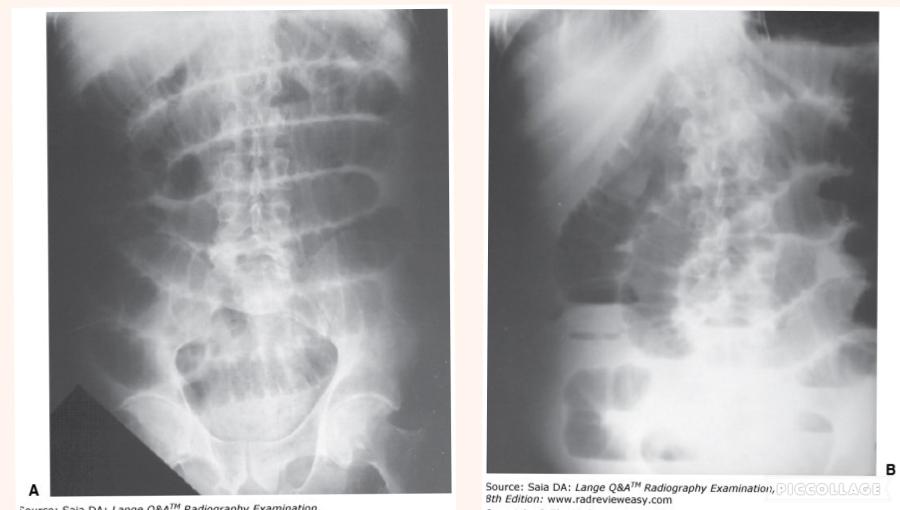

The position illustrated in the figure below can be used successfully to demonstrate the

- PA oblique sternum

- barium-filled pylorus and duodenum

- left anterior axillary ribs

1, 2, and 3

Which of the following statements is/are true regarding Figure A?

1. The radiograph was made in the LAO position.

2. The central ray should enter more inferiorly.

3. The sternum is projected onto the left side of the thorax.

2 and 3 only